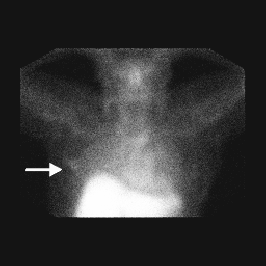

The normal intensity image (Left Image) shows, if the image is viewed at an intensity to see the liver well, little uptake is seen in the right breast. Once the image intensity is increased (Left Image), the right breast uptake is easily seen.).

Figure 1: Planar image of the uptake of 99mTc-MAb-170H.82 in primary breast cancer.